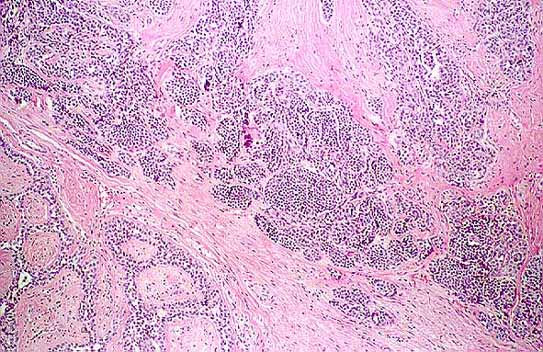

Fotos 3: Áreas de carcinoma lobular in situ en el fibroadenoma.

Foto 4: A mayor aumento proliferación de células monomorfas con pérdida de la orientación y disposición lobular.